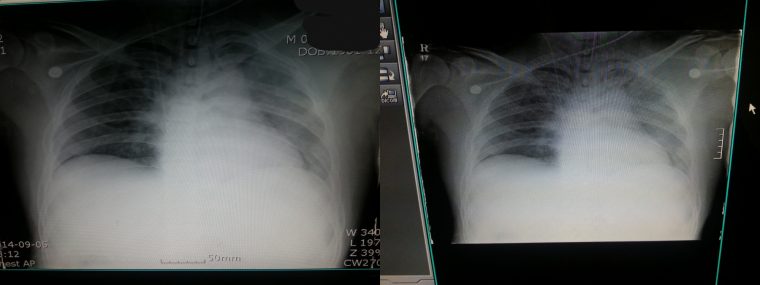

해당 게시글을 올린 작성자 A씨는 “중환자실에 3주간 무의식 상태로 입원 했던 썰”라는 제목의 글로 많은 이들의 관심을 끌었다.

글 작성자A는 사고나서 3주 동안 무의식으로 중환자실에 입원했다가 일주일 후 의식이 돌아왔으나 몸은 움직일 수 없었던 이야기를 풀었다.

아래는 해당 글 작성자가 쓴 글.

대단한 얘기는 아니지만 중환자실에 3주동안 무의식으로 있었던 썰 풀어볼게